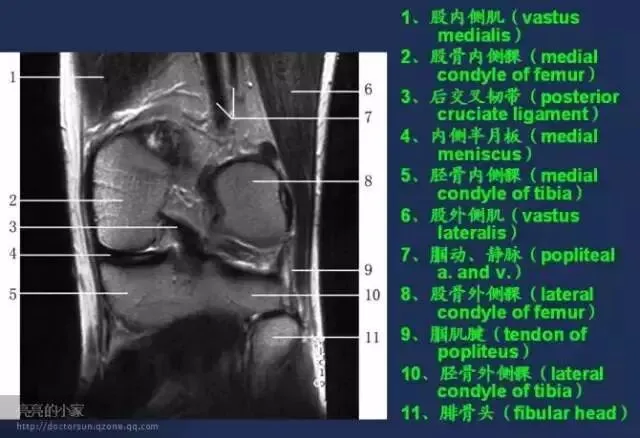

收藏!全身MRI解剖图谱,医生必备